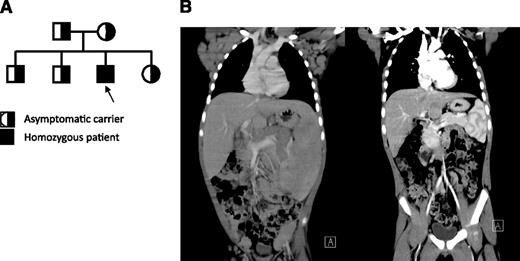

The patient is a Hispanic male born at term in 2005 to parents without known consanguinity; however, the families of both parents have been inhabitants of the same small town in northern Mexico for many generations (Figure 1A). His clinical history included recurrent otitis with bilateral perforated tympanic membranes and sinusitis that starting during in early childhood. He had persistent generalized lymphadenopathy and hepatosplenomegaly (Figure 1B, left), accompanied by intermittent fevers starting at 3 years of age. Hepatosplenomegaly became very prominent by 5 years of age and marked mediastinal lymphadenopathy produced a superior vena cava syndrome manifested by markedly dilated chest veins. He had an intermittent facial rash in a butterfly distribution and confluent erythematous macules over the trunk and extremities but no other evidence for vasculitis or glomerulopathy. The patient had several autoantibodies at high titers, which are listed in Table 1. These autoantibodies (extractable nuclear antigens [ENAs]) had not lead to disease-specific manifestations other than a period of lupus-like rash. Shortly after this, he was started on immunomodulatory treatment.

Clinical, immunological, histopathological, and characterization of patient. (A) Pedigree of patient. Parents do not have any known consanguinity. All 3 unaffected children and both parents are heterozygous for the same point mutation in PRKCD, whereas the patient represents the only affected offspring who is homozygous for this change. (B) Coronal computed tomography scan images illustrate massive hepatosplenomegaly and mediastinal, axillary, inguinal lymphadenopathy before treatment (left) and after treatment (right).

In an attempt to reduce his lymphadenopathy, the patient was treated with corticosteroids and rapamycin, which led to a remarkable and rapid reduction in the size of his lymph nodes and resolution of hepatosplenomegaly (Figure 1B, right), as well as the transaminitis and elevated inflammatory markers.